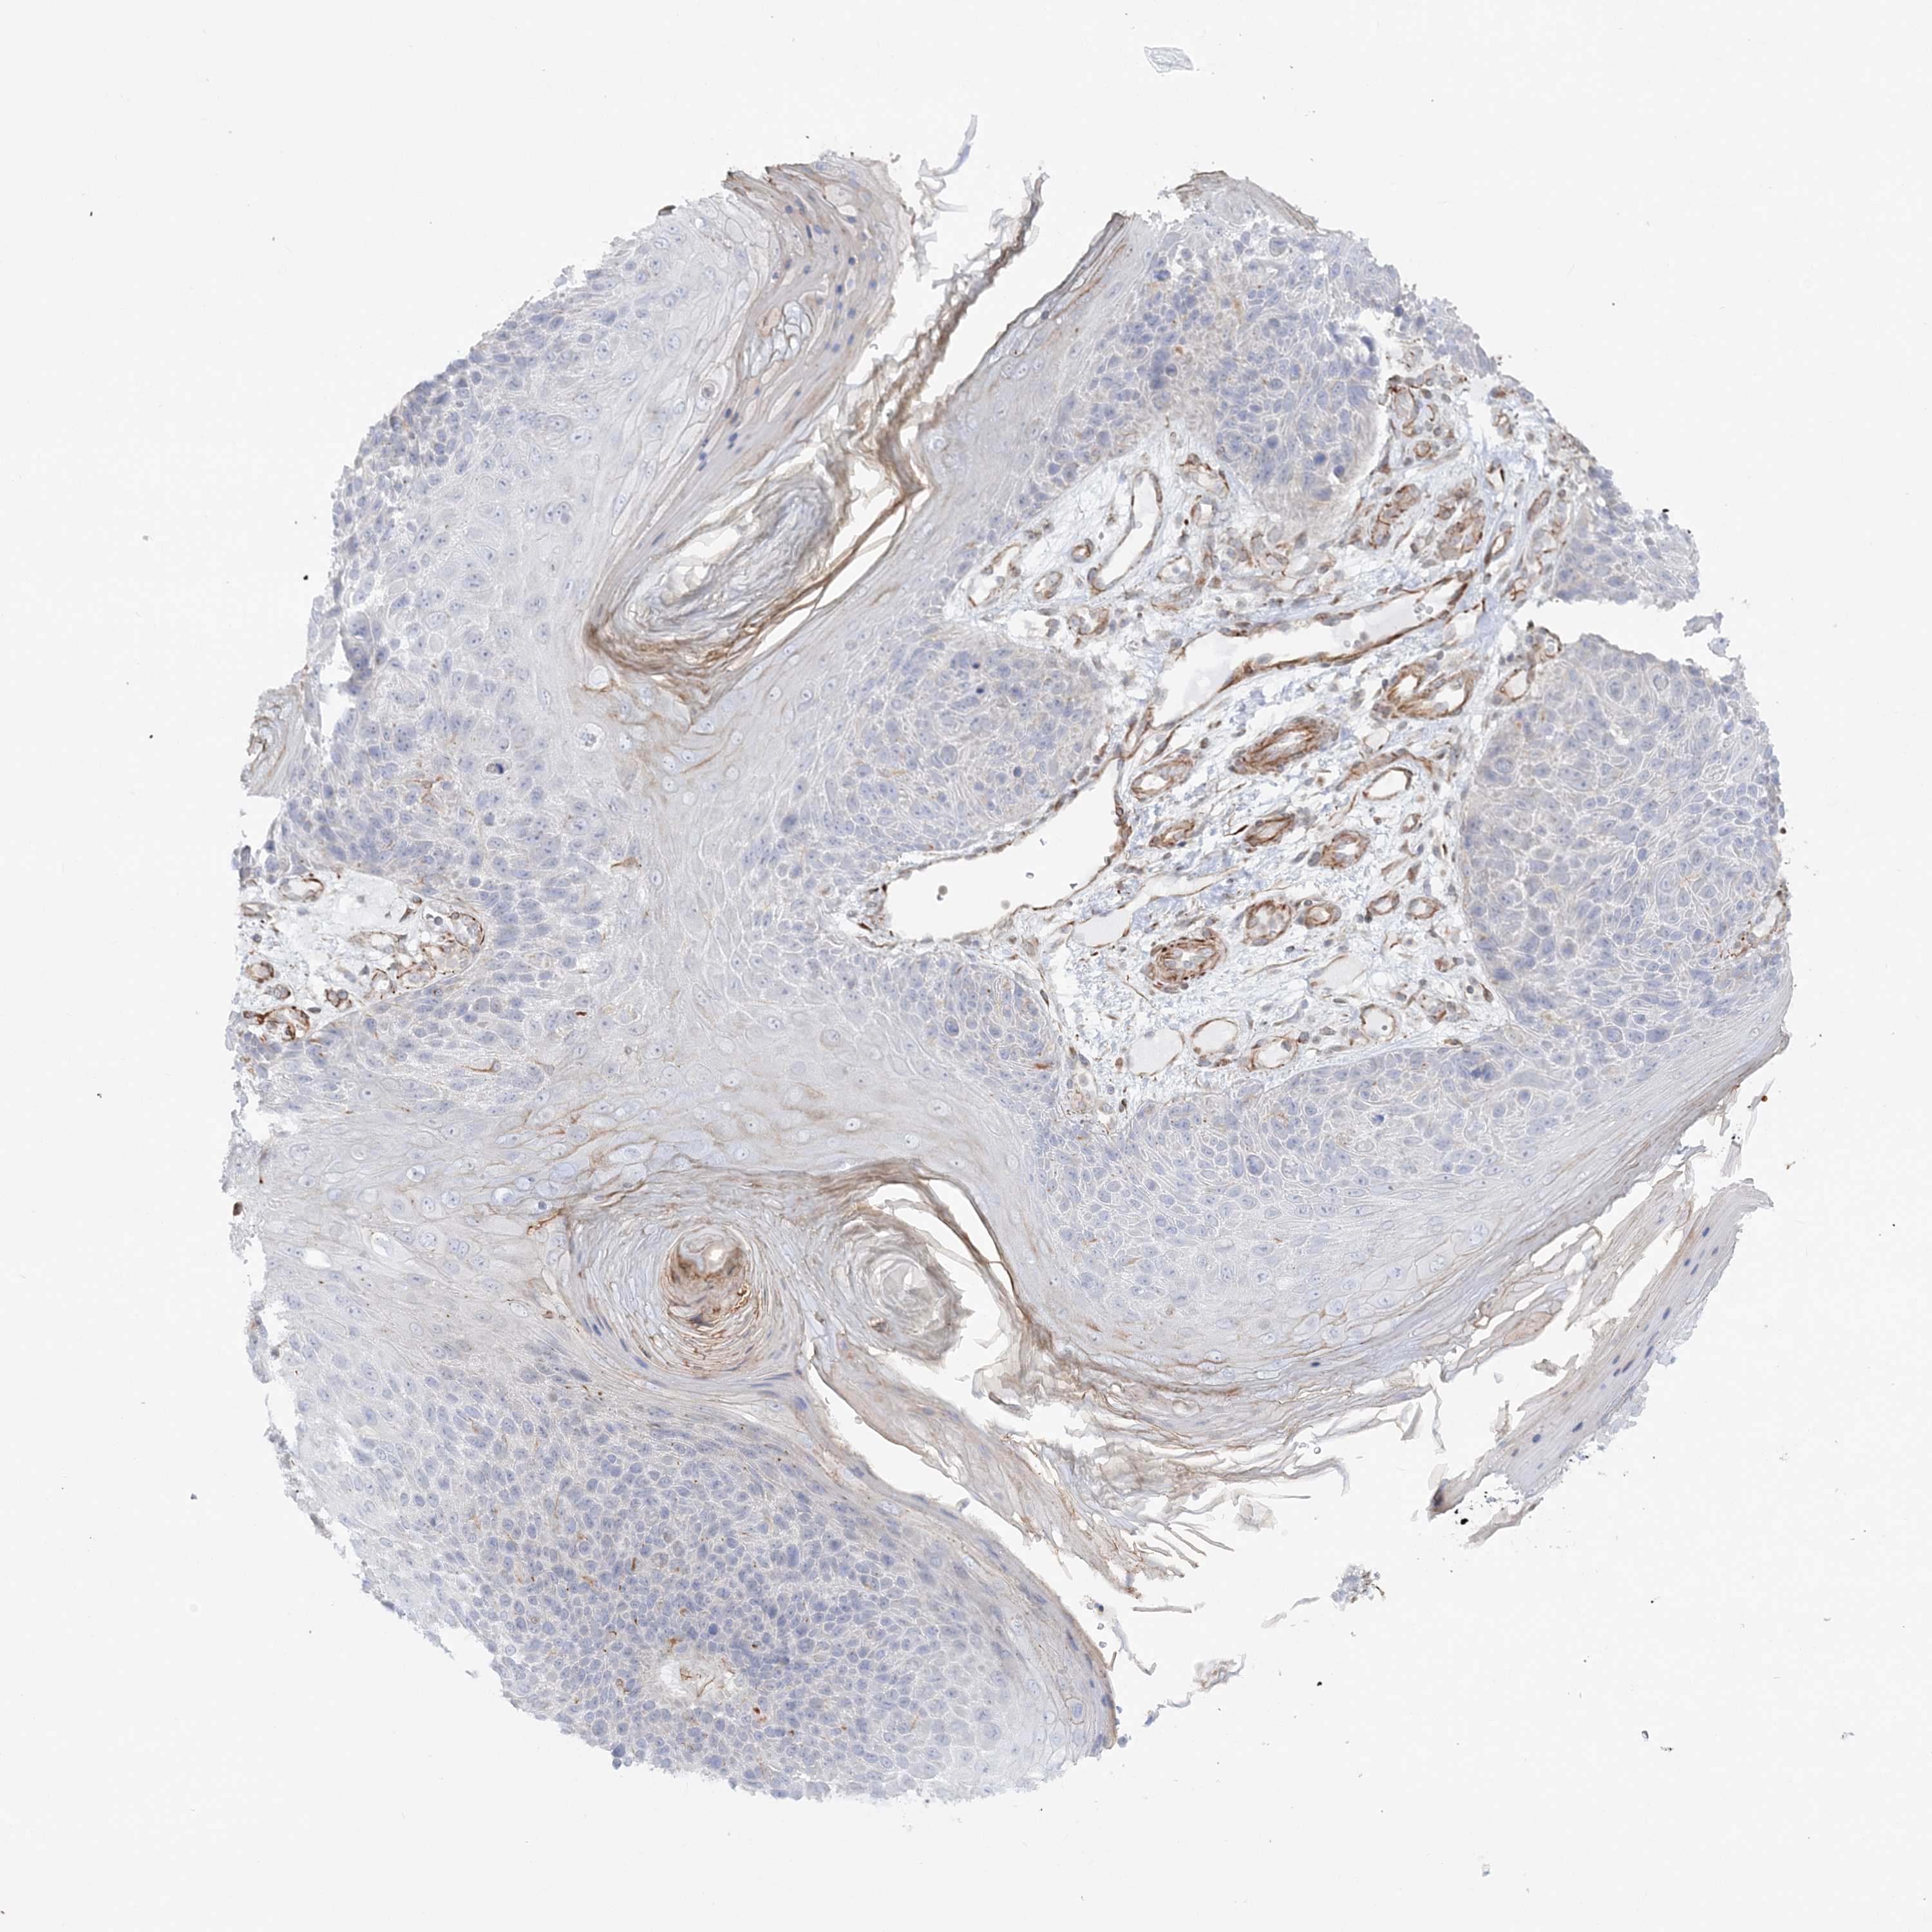

Basal cell and squamous cell cancer

SKIN CANCER - Protein expressioni

A mouse-over function shows sample information and annotation data. Click on an image to view it in a full screen mode. Samples can be filtered based on level of antibody staining by selecting one or several of the following categories: high, medium, low and not detected. The assay and annotation is described here.

Each image is clickable and will lead to virtual microscopy that enables deeper exploration of all samples and also displays staining intensity scores, fraction scores and subcellular localization as well as patient and tissue information for each sample.

Antibody HPA036560

Antibody HPA036561

Basal cell carcinoma